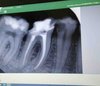

• Эндодонтическое лечение под оптикой (в т.ч. с использованием микроскопа)

• Работа с дентальным рентгеном, радиовизиографом

- Эндодонтическое лечение зубов

Анализ прицельных рентген-снимков, ОПТГ, КТ.

современные методы обработки (методика Step Back? Crown Down, система ручных и машинных Protaper) и пломбирование корневых каналов

Проведение и анализ снимков на визиографе и рентген-аппарате.